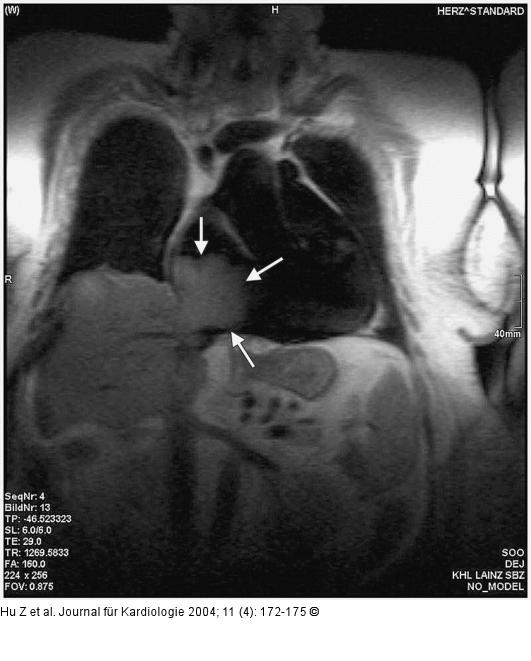

Abbildung 3: Tumorpropagation in den rechten Ventrikel MRI am Tag 3: direkte Tumorausbreitung von der Leber in den rechten Vorhof durch die V. cava inferior (koronal T1w MRI, FLASH; 1265/29/160) |

Abbildung 3: Tumorpropagation in den rechten Ventrikel

MRI am Tag 3: direkte Tumorausbreitung von der Leber in den rechten Vorhof durch die V. cava inferior (koronal T1w MRI, FLASH; 1265/29/160) |